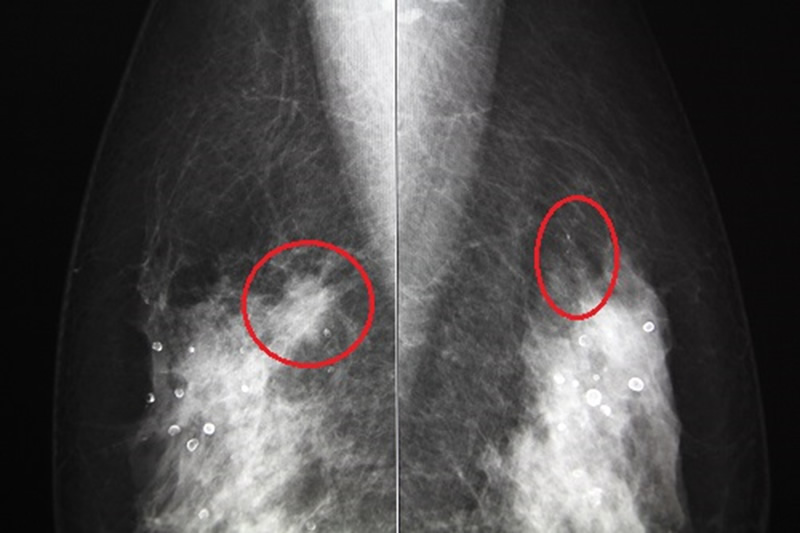

乳がんを診断する方法として、マンモグラフィと超音波の2つがあります。

マンモグラフィは石灰化がよくわかる反面、背景の乳房の濃度により腫瘤を見落とされる可能性があります。正常な乳腺組織はマンモグラフィで白く映りますが、腫瘍も白く映ります。正常乳腺と腫瘍の影のバランスで、がんがあるかどうかを判断します。乳腺組織が密な方(高濃度乳房)は、マンモグラフィで小さな腫瘤があっても見落とされる可能性があるのが問題です。